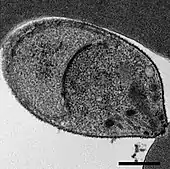

A Plasmodium knowlesi merozoite attaching to a red blood cell

As an apicomplexan, P. knowlesi has several distinctive structures at its apical end that are specialized for invading host cells. These include the large bulbous rhoptries, smaller micronemes, and dispersed dense granules, each of which secretes effectors to enter and modify the host cell.[6][7] Like other apicomplexans, P. knowlesi also has two organelles of endosymbiotic origin: a single large mitochondrion and the apicoplast, both of which are involved in the parasite's metabolism.[8]